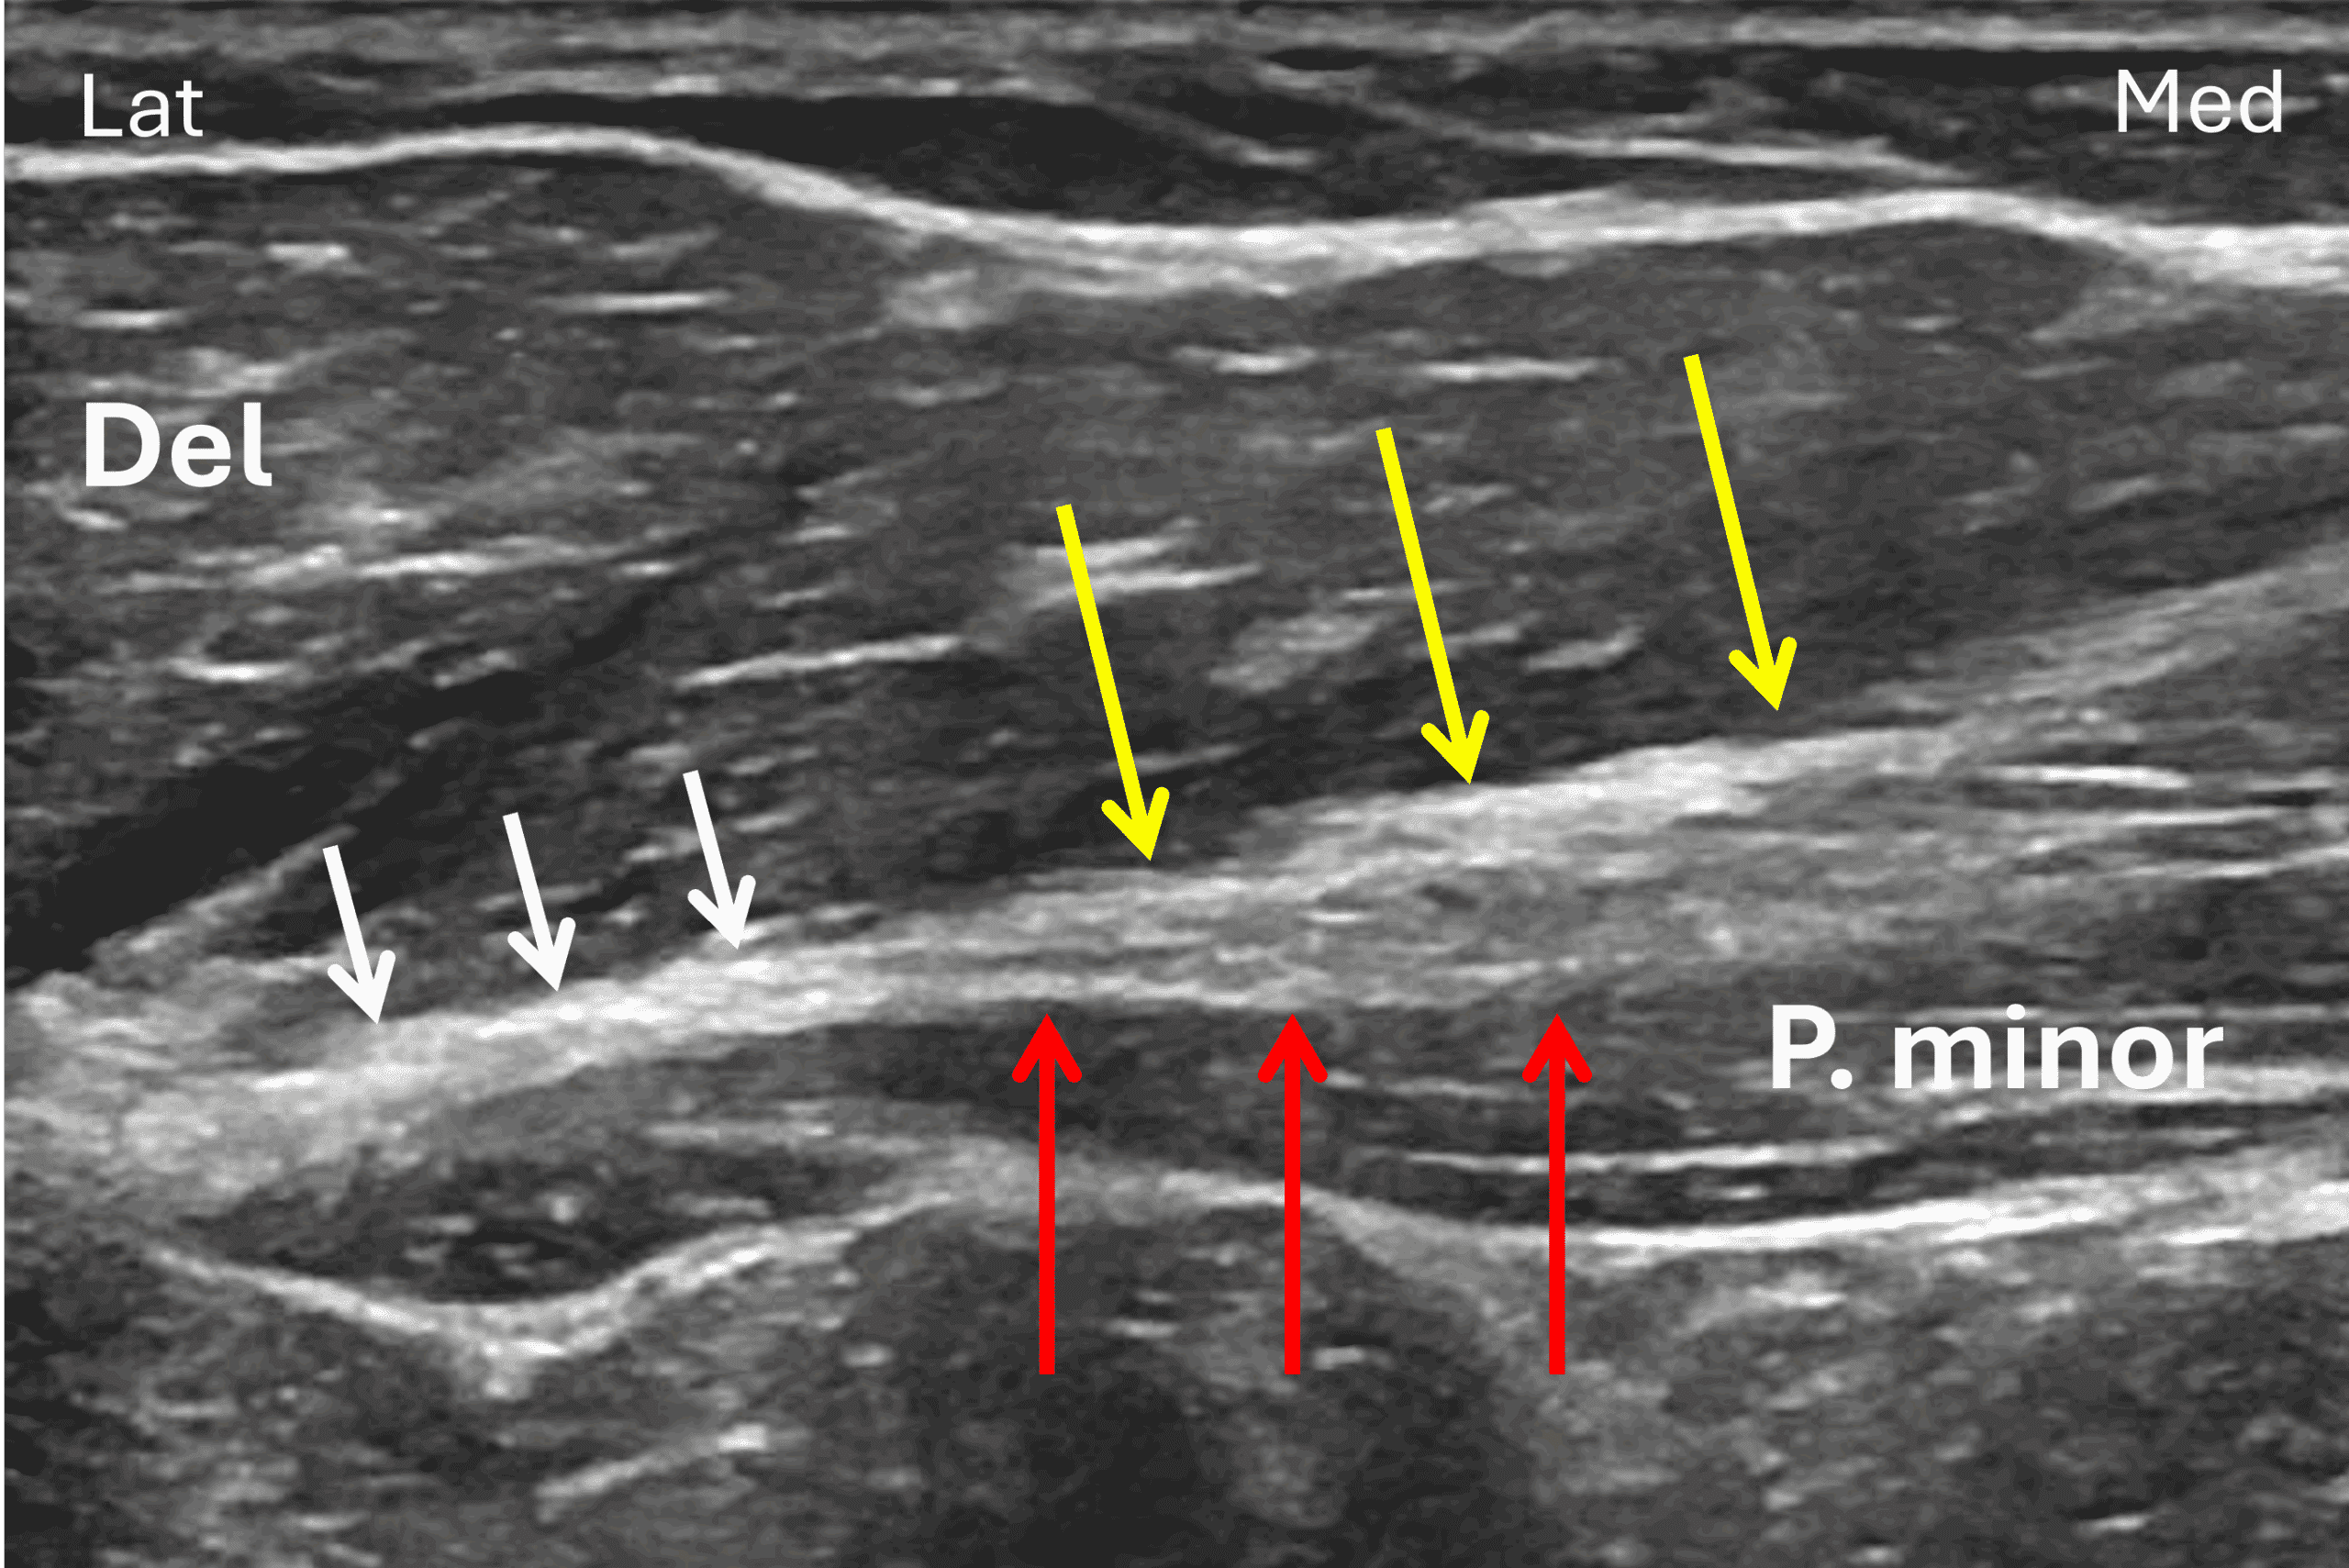

Imaging has an essential role in visualizing tear location and establishing surgical candidacy in both acute and chronic settings. To help characterize PM tears, various imaging modalities provide complementary information. Ultrasound offers high spatial resolution able to resolve the bilaminar tendon anatomy (Figure 7) and allows dynamic imaging and easy contralateral comparison. Radiographs are sensitive to subtle cortical avulsion fractures of the humeral enthesis. MRI allows imaging of the entire pectoralis muscle and tendons as well as the surrounding structures in the chest wall with very high contrast resolution.17 A recent large MRI-surgery correlation study established that MRI accuracy in predicting PM tear location is greater relative to prediction of tear thickness/number of layers involved.3

Figure 7: Transverse ultrasound of a normal pectoralis major tendon. Lat = lateral, M = medial. The clavicular head tendon (yellow arrows) contributes to the anterior tendon leaflet and is seen merging with a tendon of the sternal head (red arrows), forming a bi-layered structure (see Figure 4 and 6). In this subject, the two layers fuse (white arrows) before inserting on the humerus, located to the left of this image. P. minor = pectoralis minor muscle, Del = deltoid muscle.